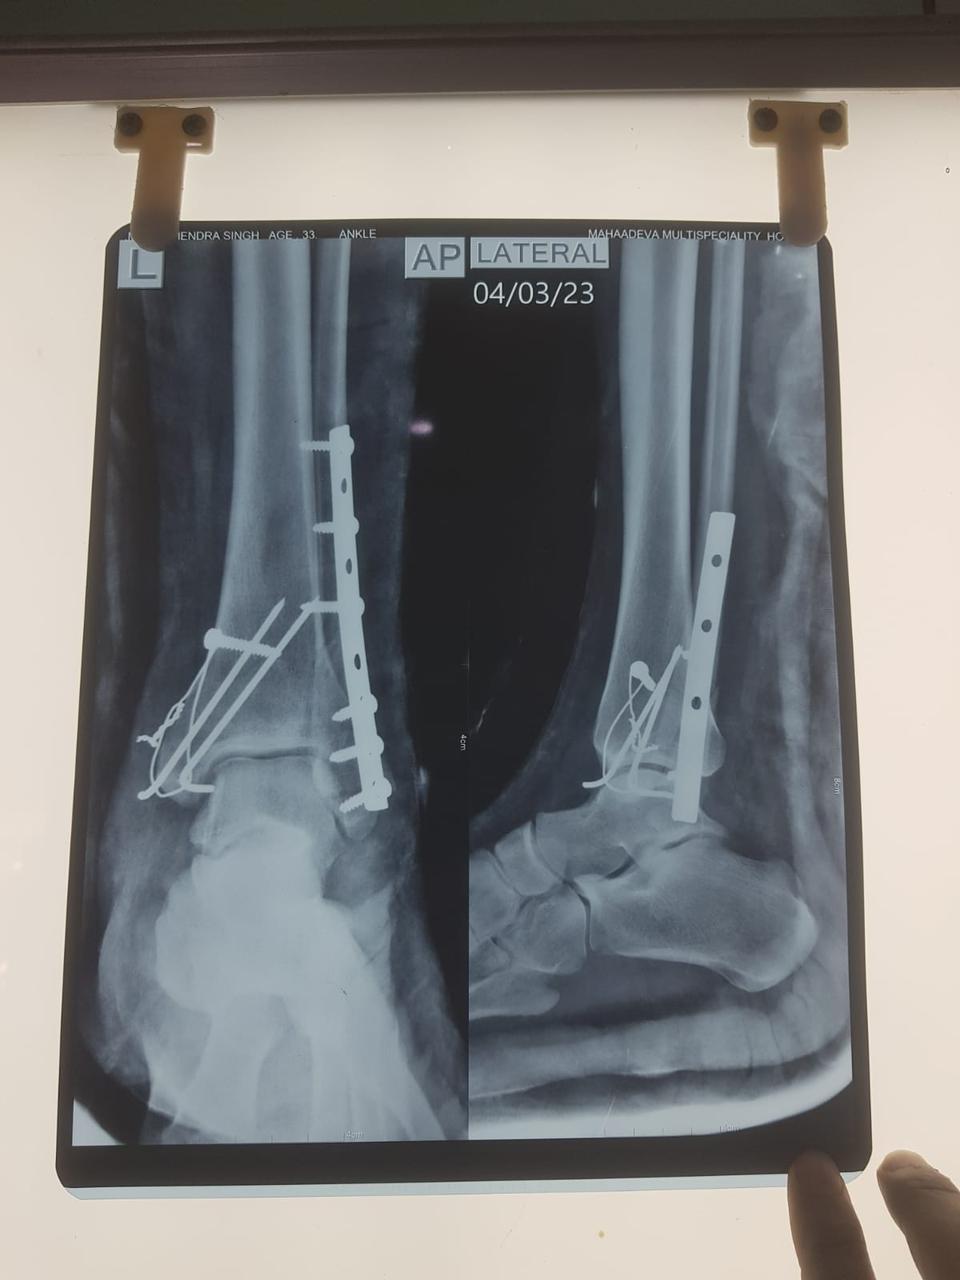

Moments That Mark Meaningful Recovery

Witness real patient transformations at The Ortho Clinic through images that reflect successful treatments and restored mobility.